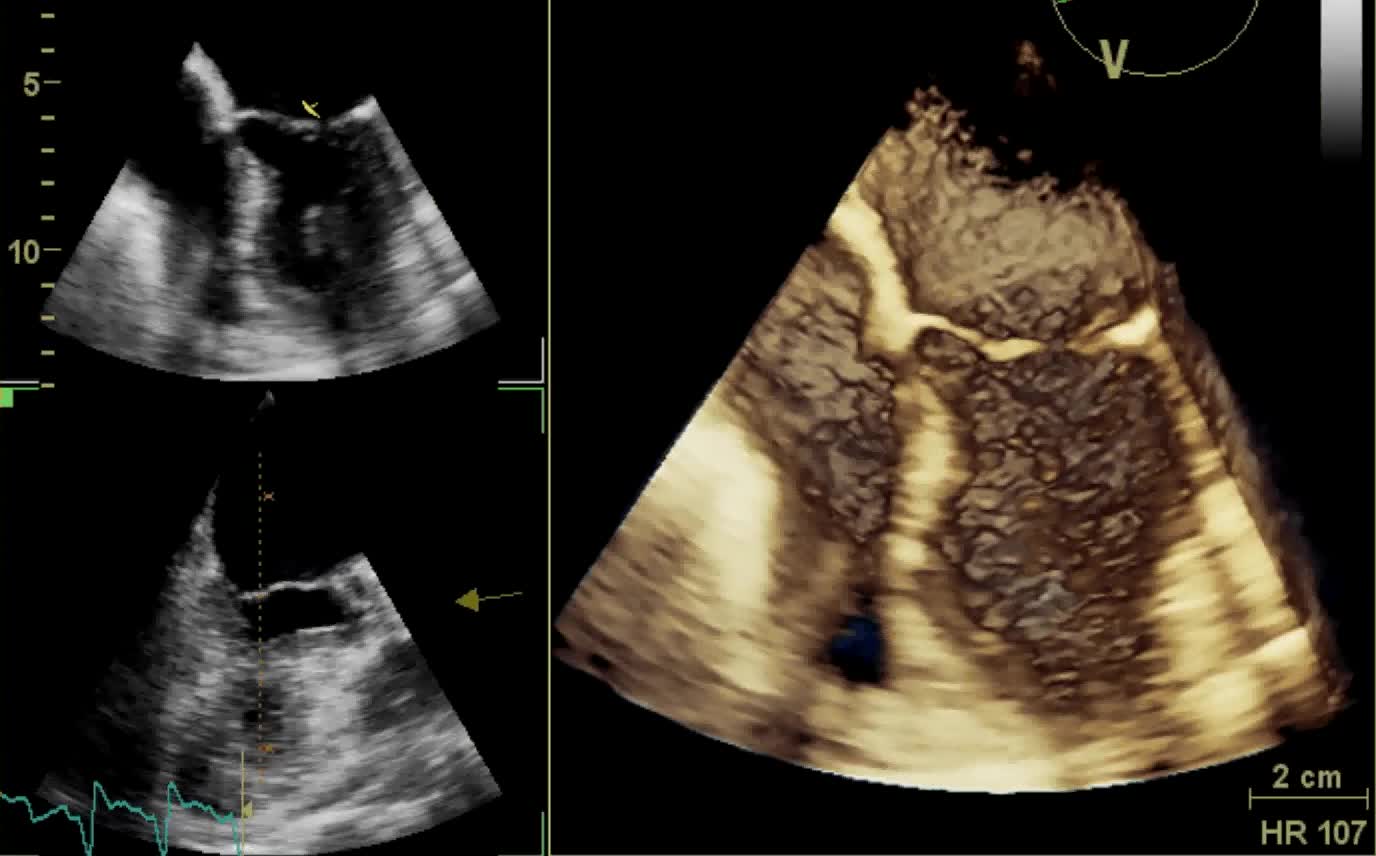

Il ruolo clinico dell’ecocardiografia in 4D

Autore:

Francesco Faletra